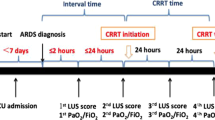

The lung ultrasound scores of the patients were obtained at different periods, including at the initiation of ECMO, each morning in the following four days and at the termination of ECMO and ventilation as T0, T24, T48, T72, T96, TW and TR. According to the above periods, the corresponding ventilator parameters and the blood gas analysis results of the right upper limb artery blood sample were also recorded, including PaO2/FiO2, PaCO2, and pulmonary dynamic compliance (Cdyn).